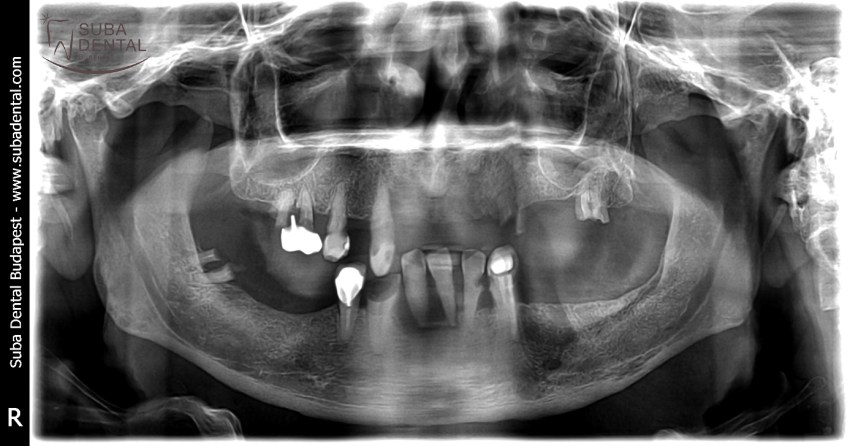

Panoramic radiograph of chronic dental foci, teeth affected by periodontal disease, and root remains. All teeth had to be extracted